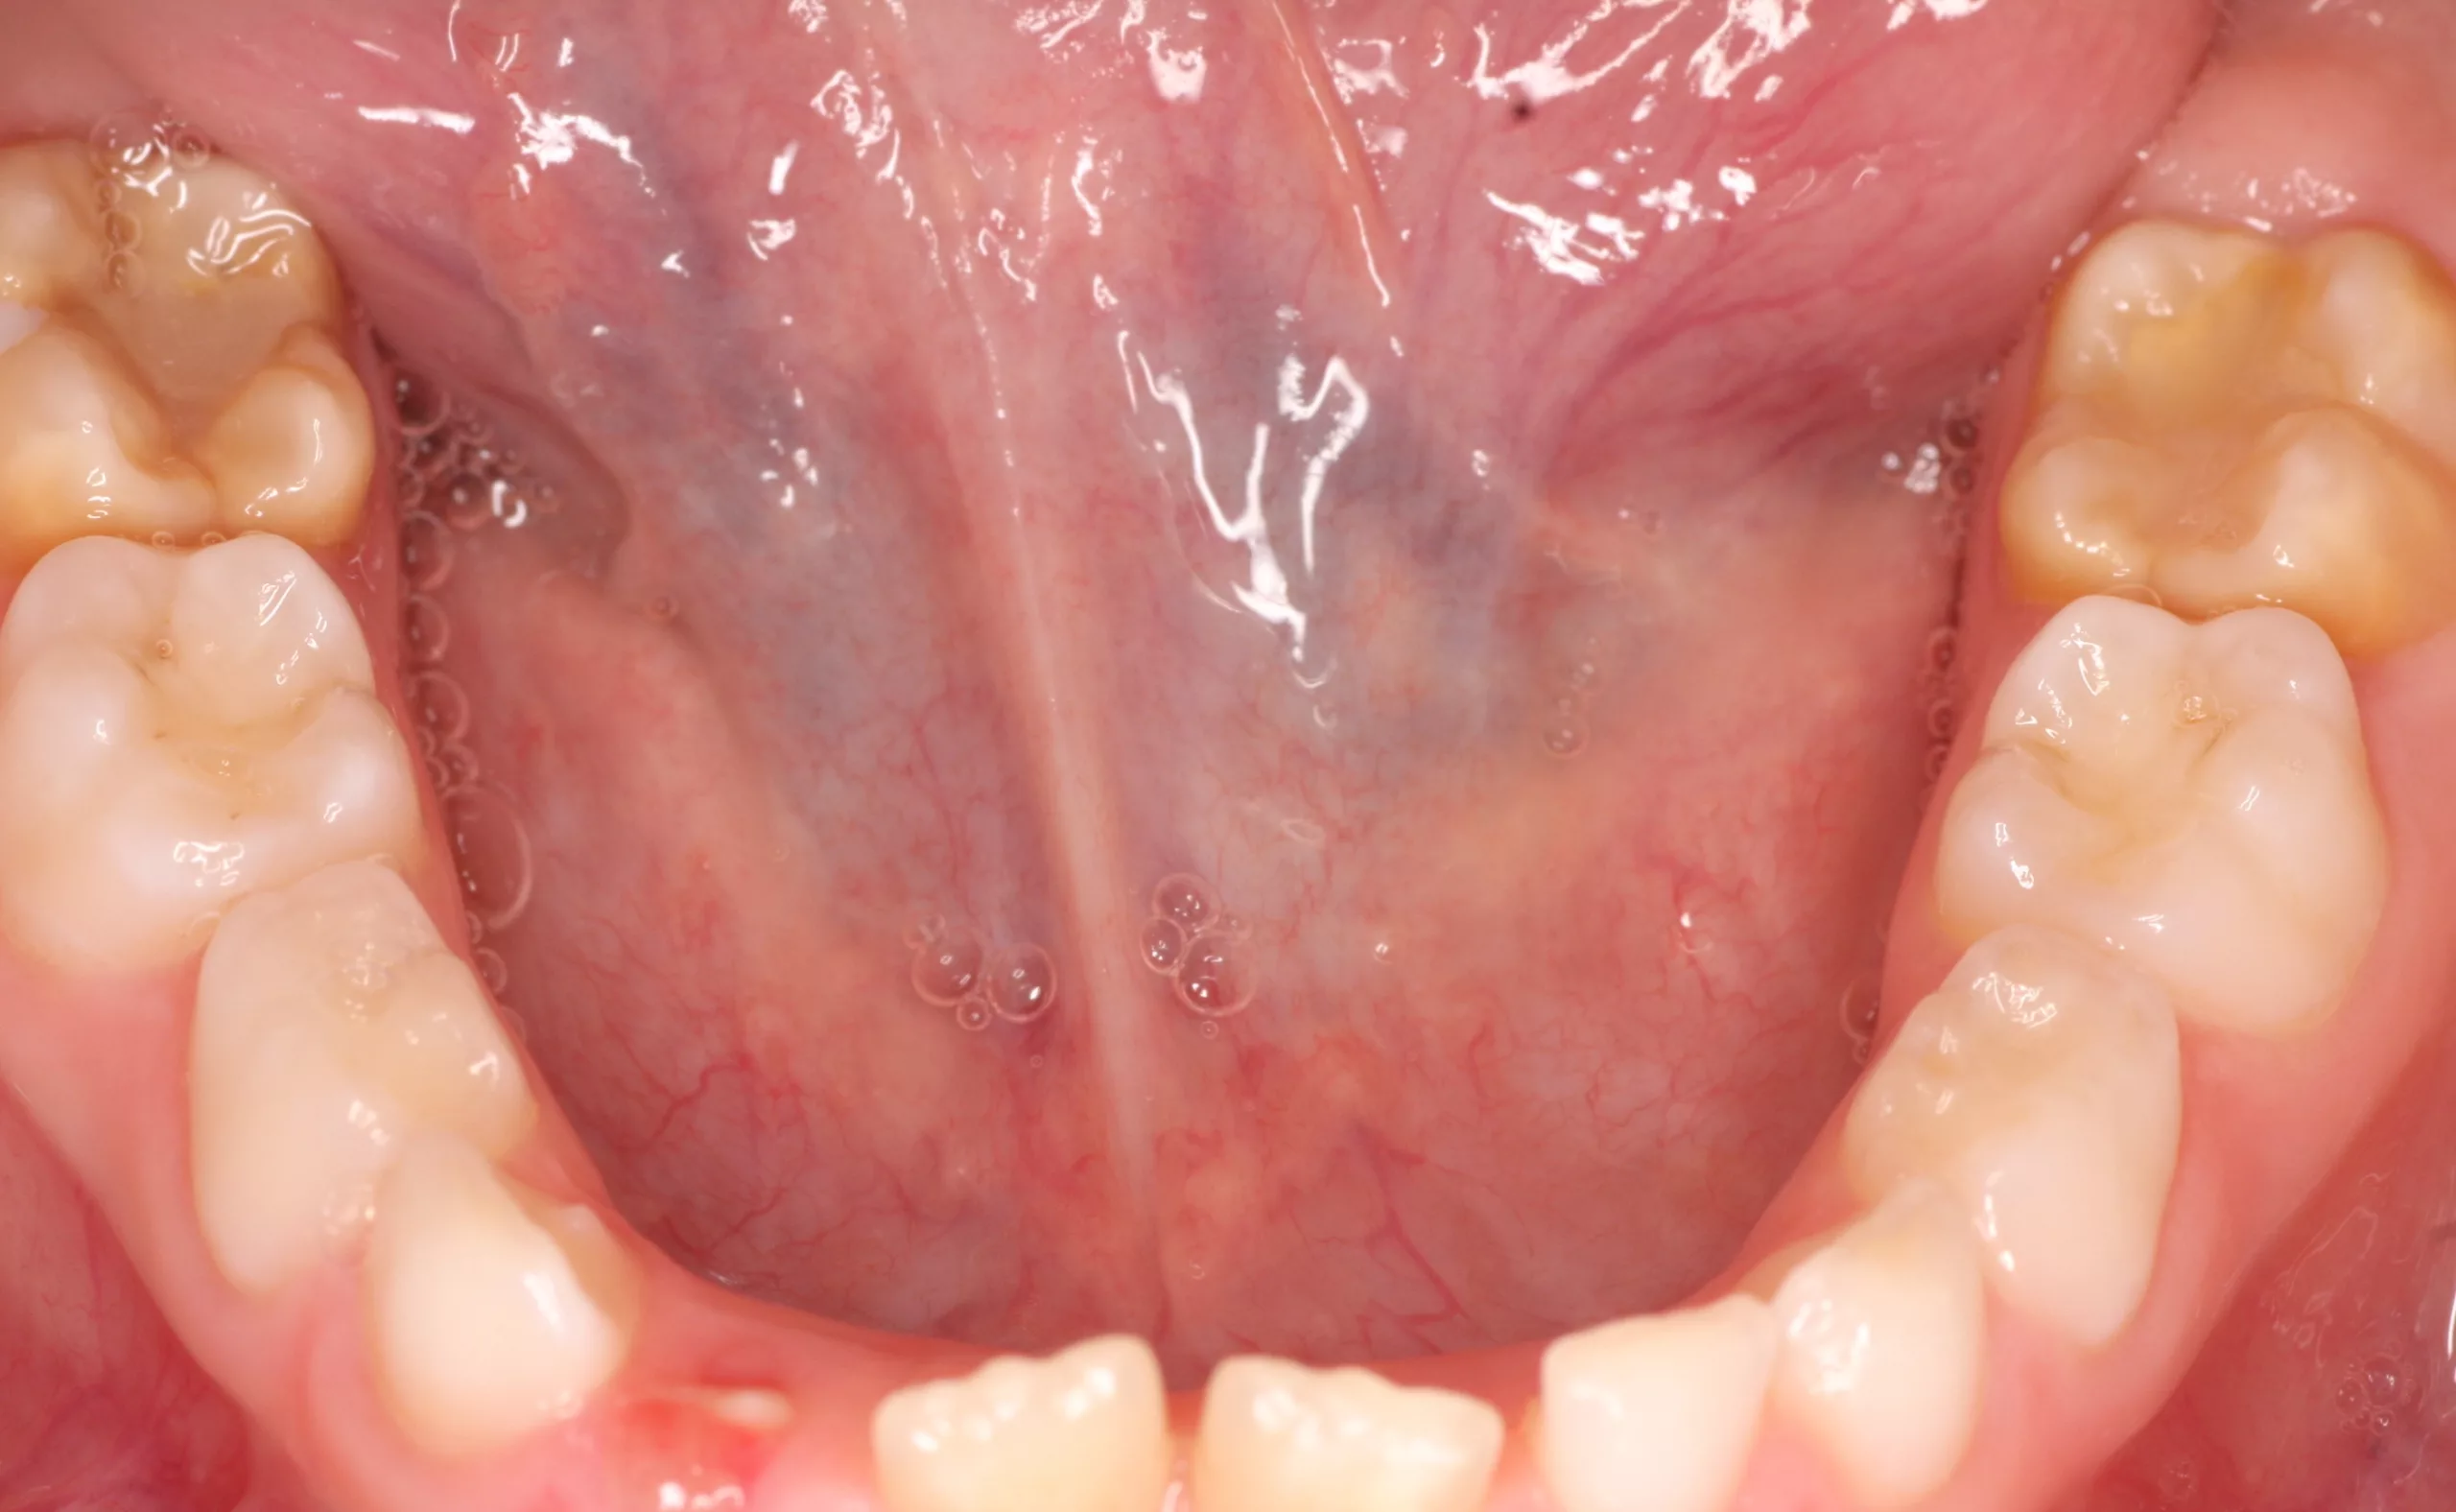

Der Begriff der „Molaren-Inzisiven-Hypomineralisation“ wird seit dem Kongress der European Academy of Paediatric Dentistry (EAPD) [1] im Jahre 2001 verwendet. Dieser beschreibt eine systemisch bedingte Hypomineralisation von ein bis vier bleibenden ersten Molaren mit oder ohne Beteiligung der Inzisiven [2] (Abb. 1 u. 2).

Klinisch imponieren die betroffenen Zähne durch abgegrenzte, weiß-cremige bis gelb-braune Verfärbungen bis hin zu prä- und posteruptiv entstandenen Schmelzdefekten mit zum Teil ausgeprägten Porositäten [2, 3]. Die Molaren sind dabei häufiger und ausgeprägter befallen als die Schneidezähne. Zu ergänzen ist, dass das klassische Bild des Befalls der Molaren und Inzisiven in der Zwischenzeit korrigiert wurde, da vereinzelt als MIH beschriebene Defekte mittlerweile auch an anderen Zähnen der bleibenden Dentition (7er, 5er, 3er) beobachtet worden sind. Des Weiteren finden sich vermehrt auch Hypomineralisationen an den zweiten Milchmolaren und den Milcheckzähnen [4, 5].